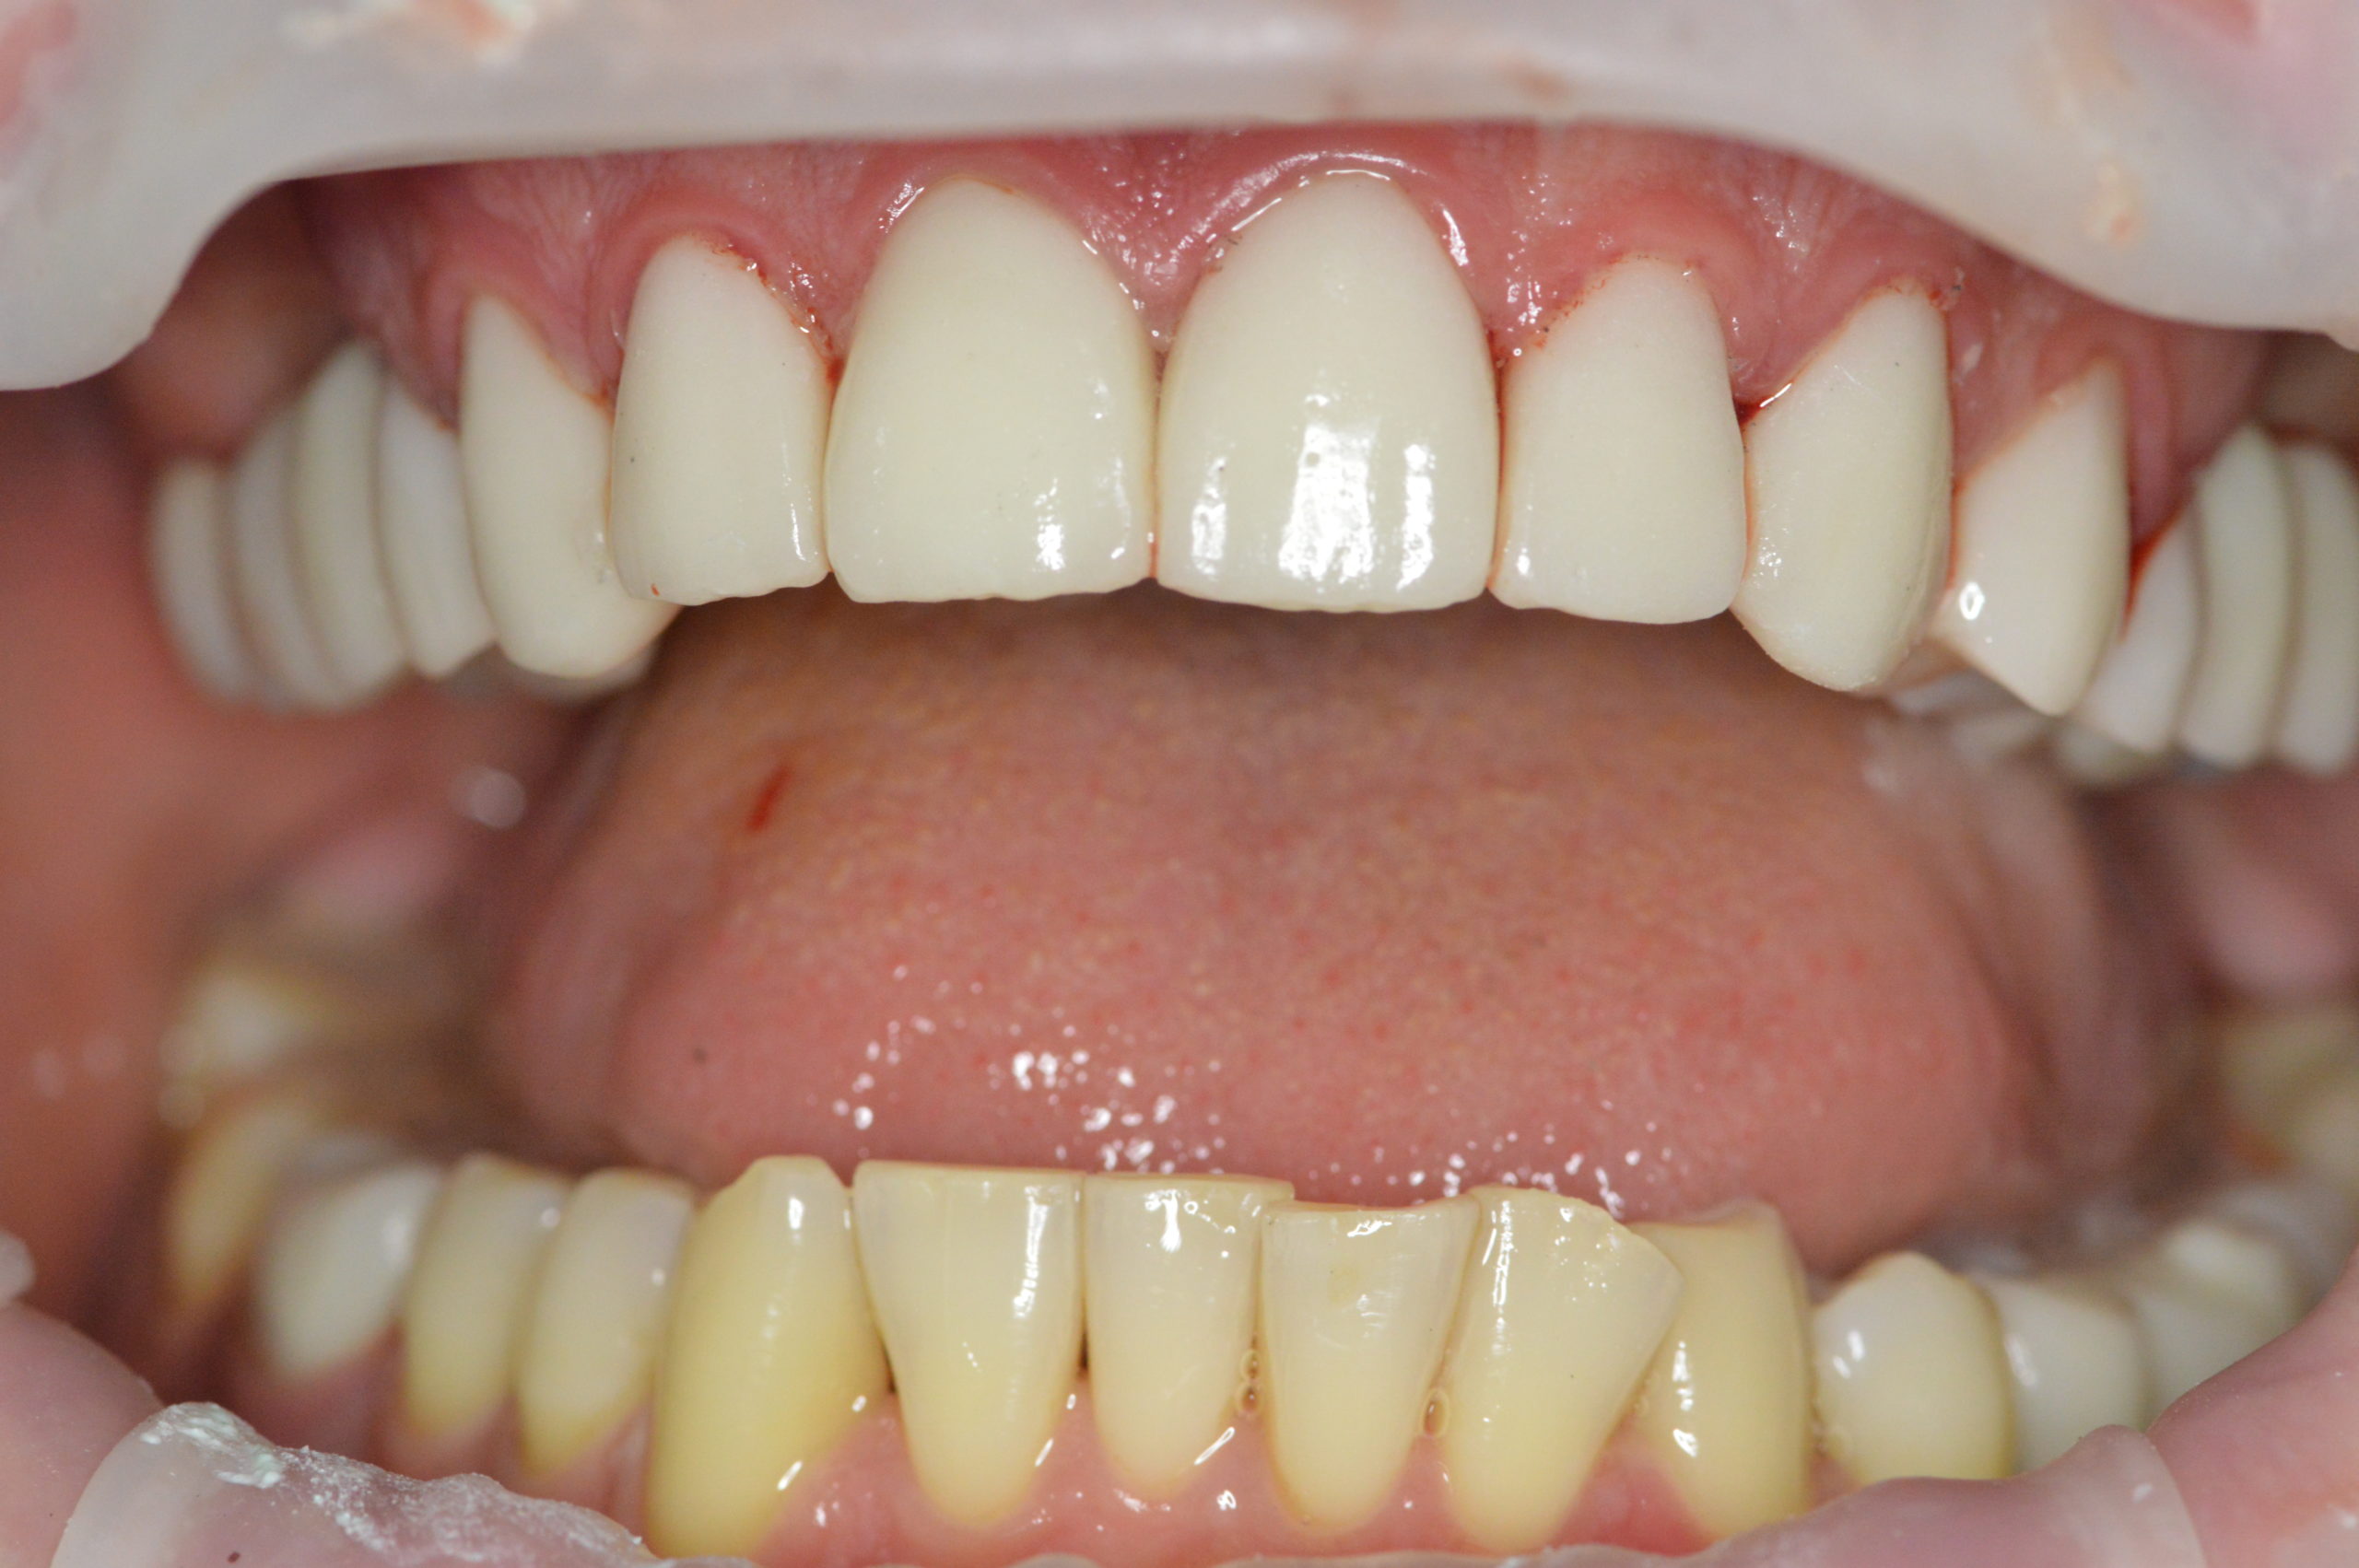

Photo AFTER treatment with dental implants and dental crowns

After next visit Mr. Peter left our clinic with this beautiful and natural looking smile. His upper jaw was fully reconstructed using dental implants in combination with dental crowns. Lower jaw was treated with 2 dental implants and two zirconium dental crowns.

Peter continues to visit our clinic to get treatment for his lower teeth. We already done 3 fillings and one root canal treatment. We are happy that we could help Peter achieve good looking and healthy smile.